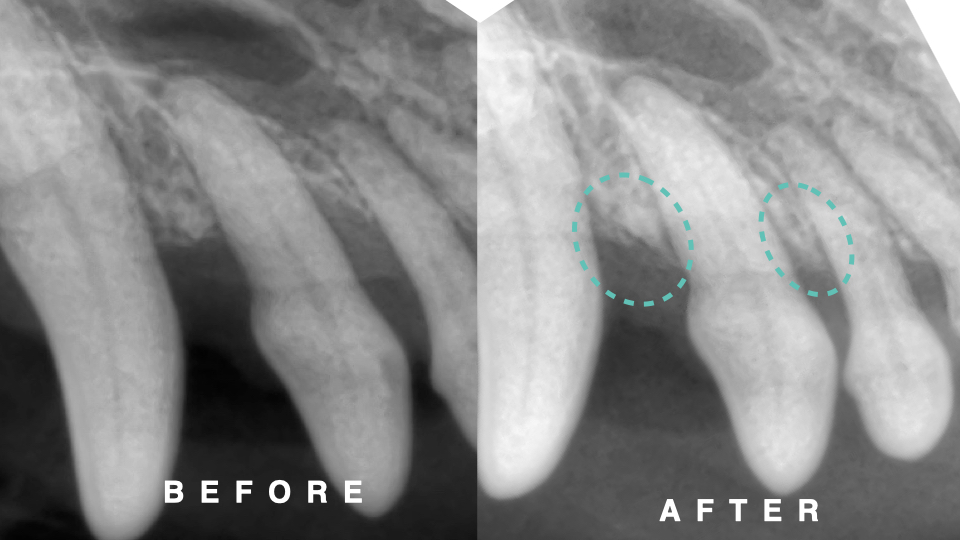

下の写真は処置時の歯槽骨と術後6ヶ月の歯科レントゲン写真です。

上顎第三切歯の歯槽骨が再生している所見が認められます。

診断は重度歯周病(AL58%)から軽度歯周病(AL22%)まで改善しました。